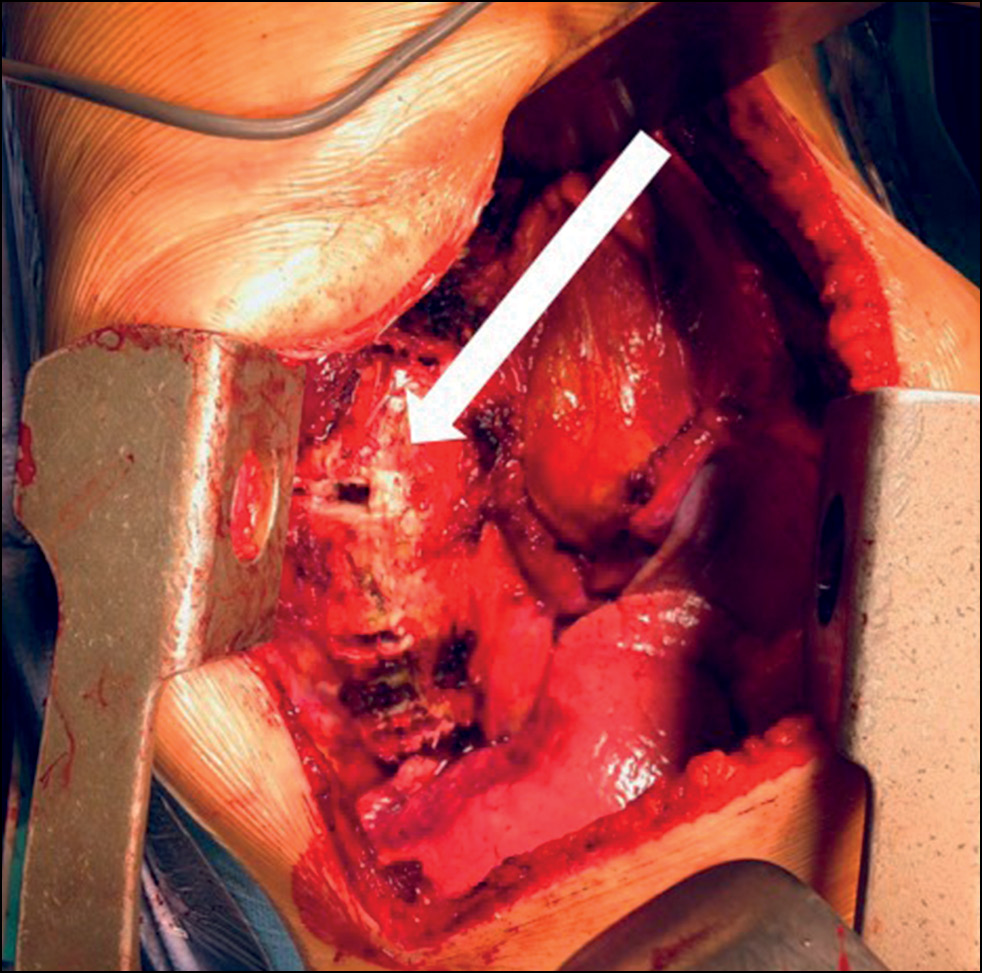

Surgical technique

The procedure was performed via a thoracotomy (mini) approach, which requires the removal of a portion of the rib. This method is similar to the classical anterior approach in treating spondylosis. The incision was made in the ninth intercostal space, as is standard practice in thoracic surgery. This approach allows for screw placement from Th8 to L1 and through three ribs above for screw placement in Th5–7. One screw was placed at the levels of Th5–6. The pleura was dissected from the anterolateral surface of each vertebral body just in front of the heads of the ribs along the length of the planned fixation. The segmental vessels were coagulated. Lumbar/thoracolumbar access was performed along the upper edge of the 10th rib, and the costochondral junction was dissected. For thoracolumbar access, the incision can be extended in the direction of the external oblique abdominal muscle approximately 3–5 cm anteriorly. The incision length was depended on which part of the lumbar spine must be visualized. Subsequently, standard retroperitoneal access to the spine with frenotomy was performed. Once the deformity apex was viewed, X-ray control of the levels was performed. In 49.3% of the cases, nucleotomy for mobilization was performed by dissecting the fibrous ring and partial removal of the pulposus nucleus (Table 1, Fig. 1).

Fig. 1. Type of surgical wound after thoracophrenolumbotomy, a nucleotomy was performed in order to mobilize the scoliotic curve in the area of planned fixation.